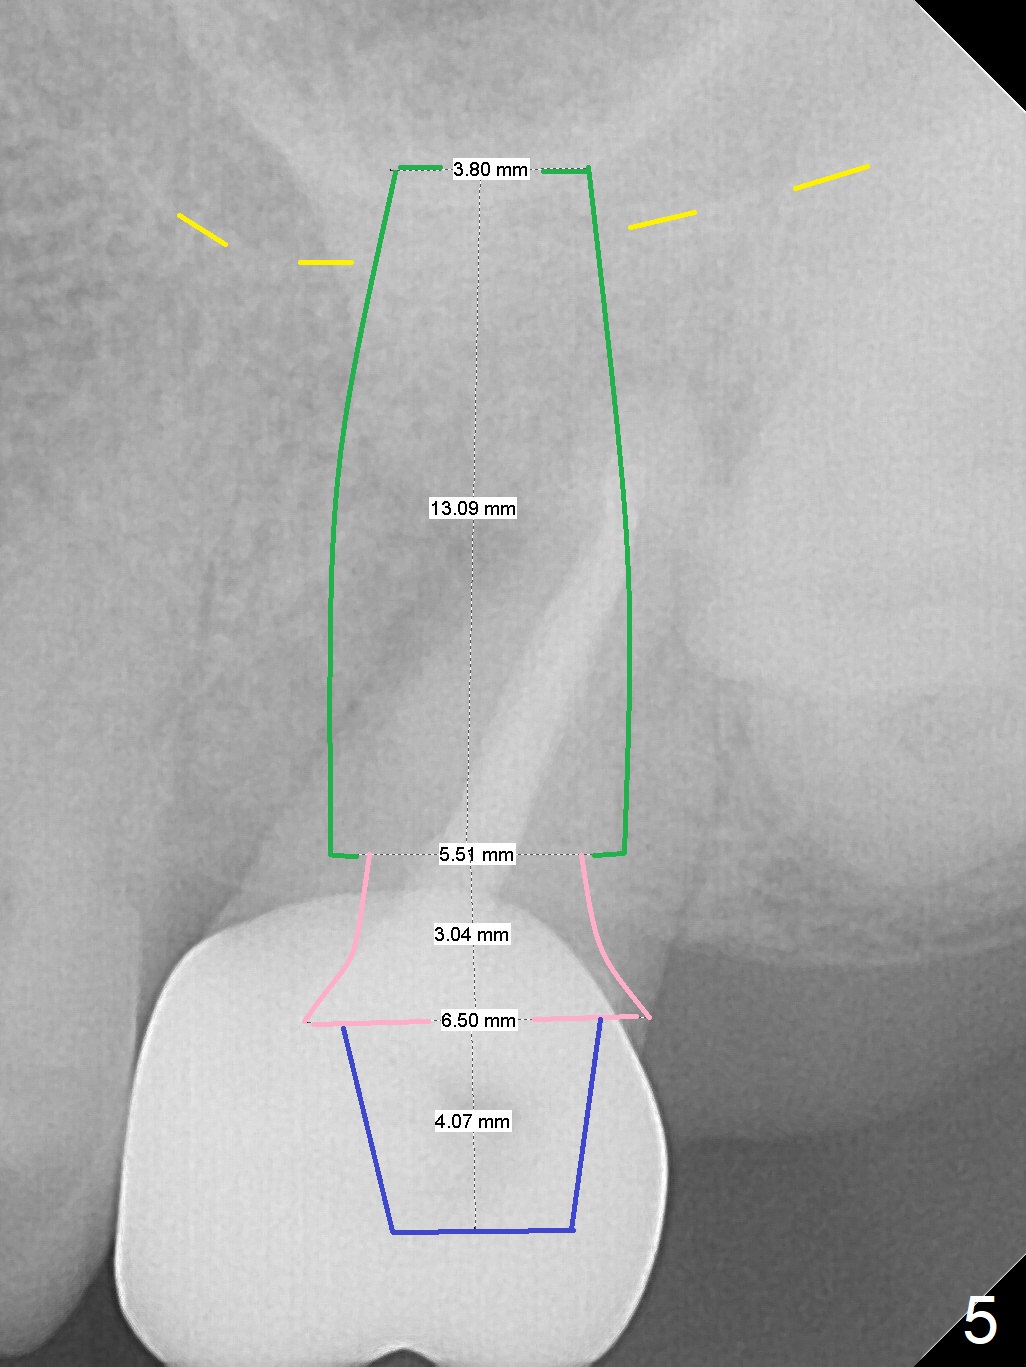

A 64-year-old woman will return for extraction/implant for the upper left 2nd molar with a fistula (Fig.1). Since the roots deviate distal (Fig.2 after extraction), initiate osteotomy in the apical 1/3 of the mesial slope with 1.5 mm drill (Fig.3). Once the lamina dura is penetrated, change trajectory (Fig.4) and extend depth for 15 mm (gingival level). After use of 2 mm drill, insert marked parallel pin for PA. The final implant as well as abutment is shown in Fig.5.